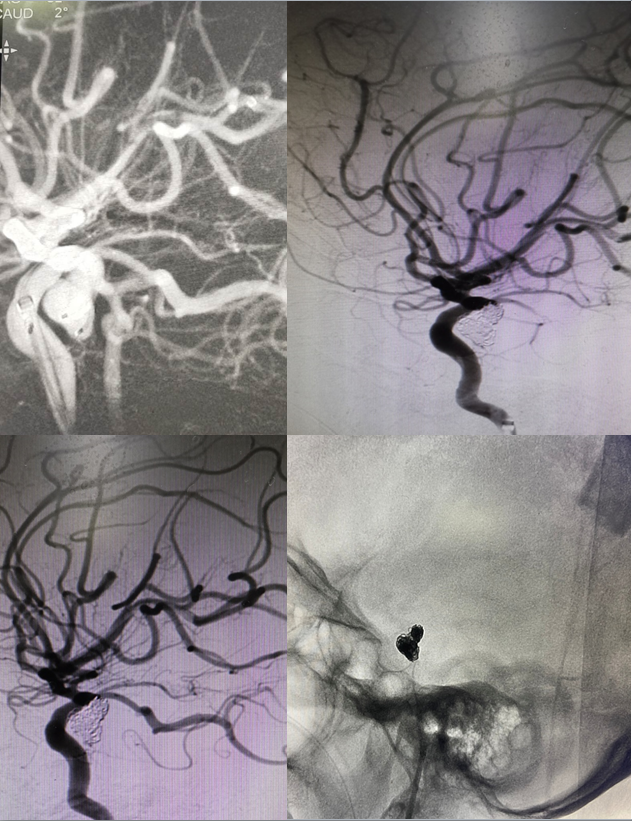

與此同時,我也更換好洗手衣,穿上我的“戰(zhàn)服”——厚重的鉛衣,規(guī)范洗手、消毒后上臺,準備股動脈穿刺、行全腦血管造影術(shù)。術(shù)中,我們發(fā)現(xiàn)患者右側(cè)后交通動脈大動脈瘤。臺上,我認真細致,貼鋼球,測量動脈瘤大小,經(jīng)過3D造影,查找工作位,調(diào)整C臂角度。臺下,林濤主任反復(fù)查看造影結(jié)果,迅速判斷,做出兩個診療方案:患者右側(cè)后交通動脈起始于動脈瘤瘤頸,單純栓塞難度較大,方案一是選擇我們已經(jīng)熟練掌握的雙微導(dǎo)管技術(shù),行彈簧圈致密填塞;方案二,支架輔助彈簧圈填塞動脈瘤,使用支架輔助栓塞,后期需要長期口服抗血小板聚集藥物治療,因此增加出血風(fēng)險,權(quán)衡之后,我們選擇了第一套方案。

根據(jù)患者病情選擇合適的神經(jīng)介入材料,林主任縝密心細,我積極配合,彈簧圈一個一個填塞,操作流暢,動作嫻熟,直至破裂出血的動脈瘤被完全填塞,我們才松了一口氣......